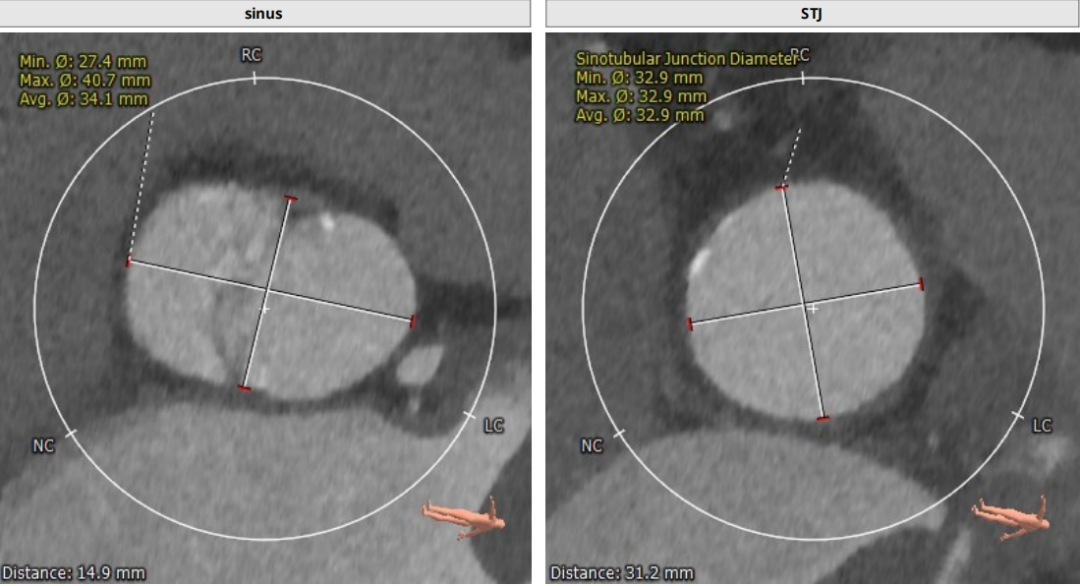

术前CT评估:

瓣环平均直径:26.8mm,左室流出道平均直径:31.2mm;

升主动脉(未见)明显扩张,心脏角度:69°;

左冠高度:12.5 mm,右冠高度:13.6 mm。

Annulus:26.8mm;LVOT:31.2mm

Sinus:27.4mm*40.7mm;STJ:32.9mm*32.9mm

升主:38.1mm*38.6mm;主动脉成角:69°

钙化积分:790